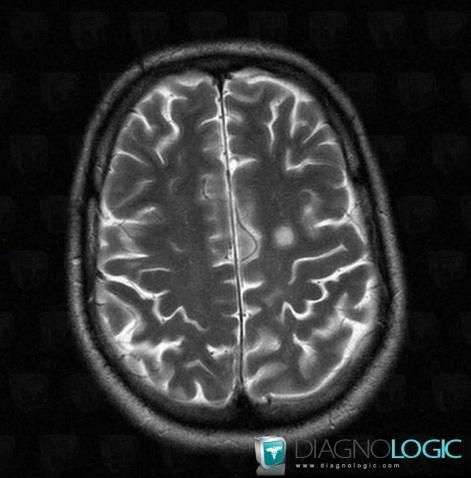

Multiple sclerosis, Ventricles / Periventricular region, MRI

Here is the specific information in the key image above:

- Diagnosis Multiple sclerosis, Location(s) Ventricles / Periventricular region, with gamuts Periventricular anomaly seen in MRI